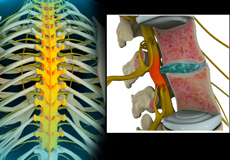

Herniated Disc (Lumbar)

Herniated disc is a condition in which the outer fibers (annulus) of the intervertebral disc are damaged causing the soft inner material of the nucleus pulposus to rupture out of its space. A herniated disc, common in the lower back (lumbar spine) occurs when there is a tear in the outer lining of the disc (annulus fibrosus). This causes the inner jelly-like material (nucleus pulposus) to leak out and place pressure on the adjacent spinal nerve root. It is the most common cause of lower back pain and pain that radiates down the leg (radiculopathy).

Lumbar Herniated Disc

A herniated disc is a condition in which the outer fibers (annulus) of the intervertebral disc are damaged, causing the soft inner material of the nucleus pulposus to rupture out of its space. It is the most common cause of lower back pain and pain that radiates down the leg (radiculopathy).

Lumbar Disc Herniation

Lumbar disc herniation is the most common cause of lower back pain and leg pain (sciatica). Aging, injury or trauma may cause the annulus fibrosus to tear, resulting in protrusion of the nucleus pulposus. This may compress the spinal nerves and/or spinal canal.

Disc Herniation

Disc herniation is a condition where the central nucleus pushes through the outer edge of the disc, causing a bulge that compresses the spinal nerves.